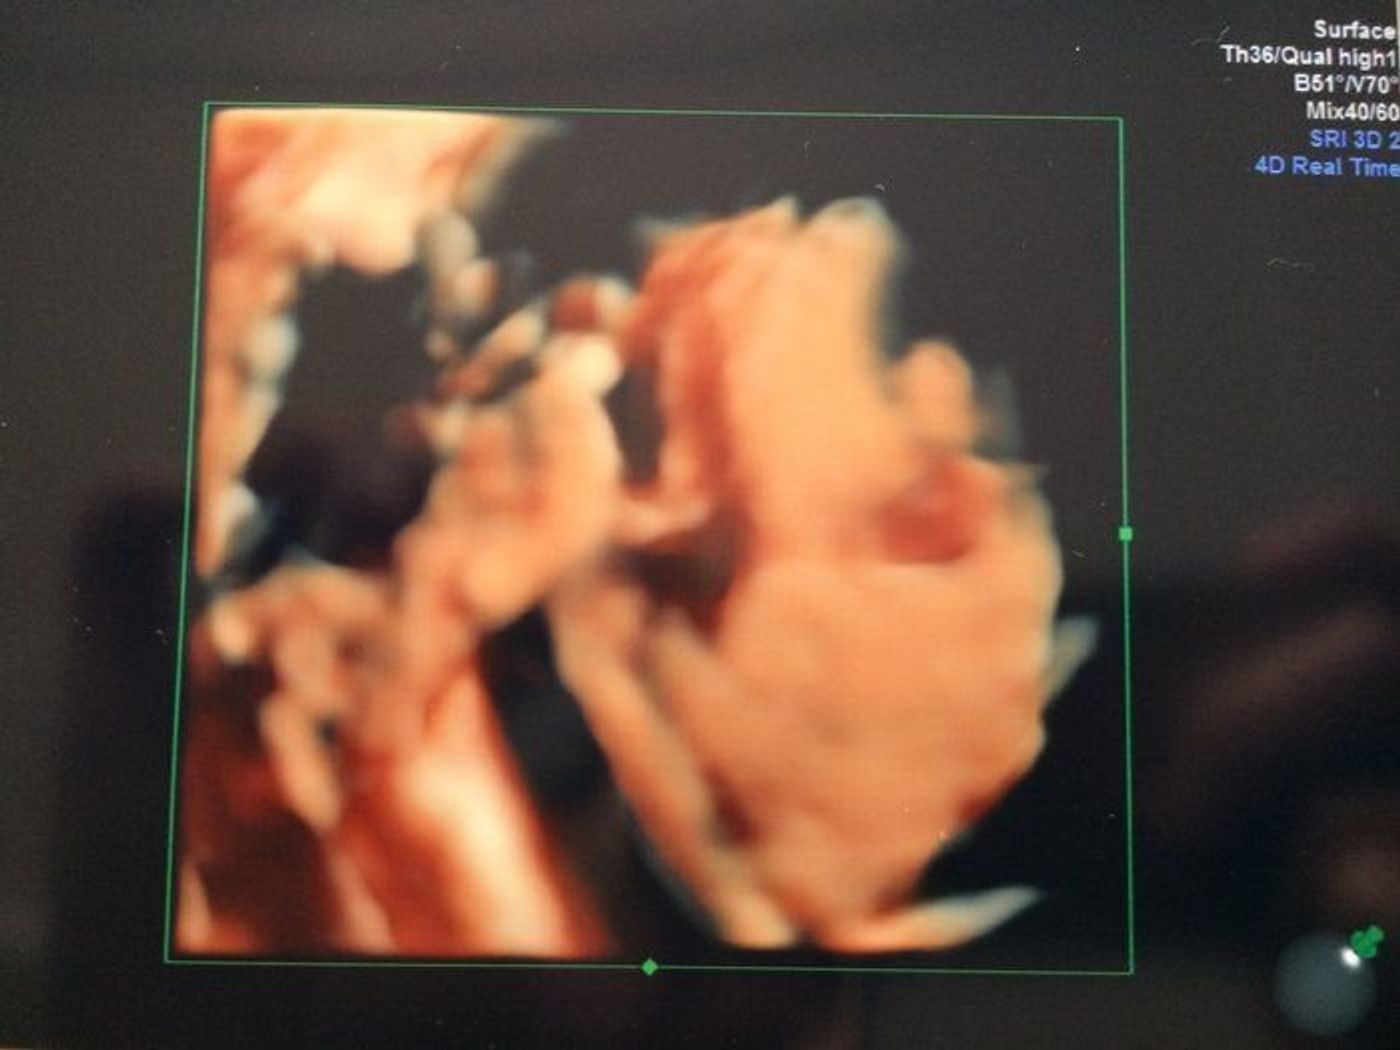

妊娠29週34日 大きな変化なく経過しました。 お腹は時々張っていましたが、 マグセントをいくほどではなく、 様子をみていました。 相変わらずシャワーにはいかず、 洗髪清拭足浴で過ごしていました。 妊娠29週5日 この日はプロゲデポーの筋肉注射と妊娠29週0日の胎児の大きさ 体重972g~1653g(*) 消化器(胃や腸)の働きがほぼ完成に近づき、ウンチがほんの少しだけ、作られ始めます。 このウンチは生まれたあとに排泄されます。 妊娠29週1日目の4Dエコー写真&胎児(赤ちゃん)の大きさ 27週0日目の妊婦健診は、年末年始の暴飲暴食直後ということもあり、体重がかなり増えていたんですが、今回は割と優秀♪ 06kgの体重増加でした。 。 。 って言っても増えてはいるんですけどね